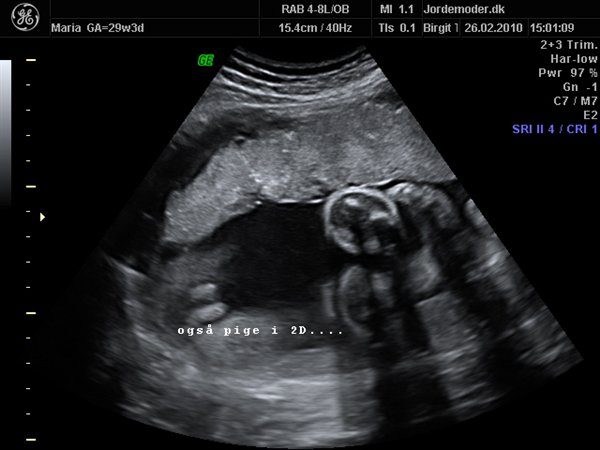

Idag har vi jo set lille pigen i 3d/4d, og hvor var det bare den mest fantastiske oplevelse..

Her kommer lige lidt billeder af vores smukke datter..